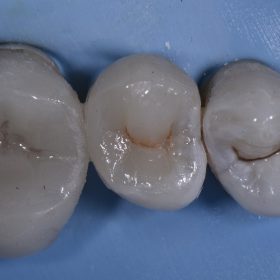

Safe Amalgam Removal | White Fillings | Invisible Fillings | Tooth Restorations | Cosmetic Dentist Auckland

Amalgams can be removed in a safe way whilst simultaneously reconstructing lost tooth structure with biomimetic (nature-mimicking) materials. Here, true artistry with composite resin is seen – striving for excellence […]